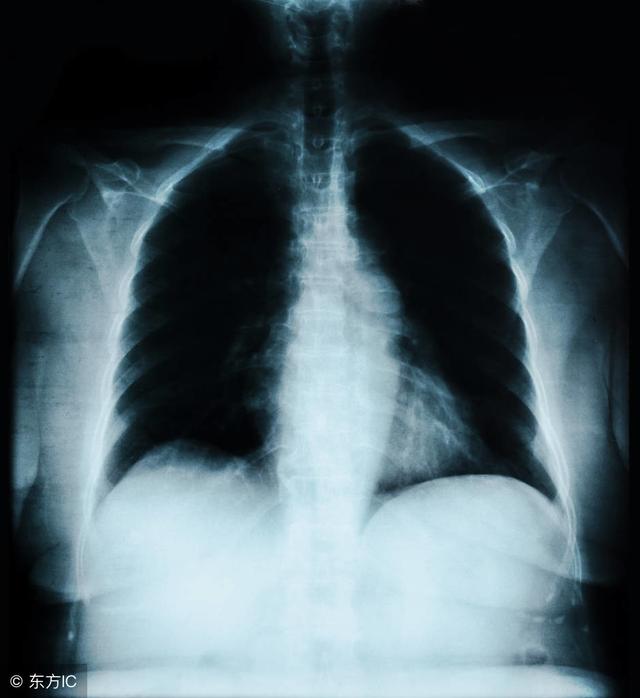

胸片上的密度增高影,可以是结节,也可以不是结节,比如索条,炎症等等,很多的病变在胸片上都表现为密度增高影。

要不要赶紧手术,会不会恶化成肺癌。简单介绍下病史:患者为47岁女性,常规体检发现右上肺结节,当时服用了消炎抗生素,但是消退不明显。